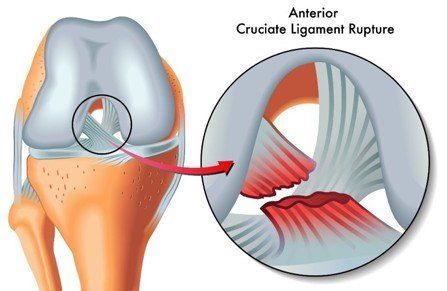

膝前十字靱帯 (ACL)損傷とは 膝には、関節の動きをコントロールする4本の靱帯があります。 前十字靭帯はそのうちの一つで、膝が伸びすぎないように抑えたり、膝の前ずれや捻りの方向への動きを制御をしています。 ジャンプの着地や急な方向転換、相手Acl術後の固有感覚の回復過程について,術後6か月で 正常な機能に戻るという報告がある4).今回の総軌跡長の 変化では,男女とも経時的に有意な減少を認め,術後6か 月以降に安定する傾向を示し,同様の結果が得られたと考 acl再建術後患者のスポーツ復帰において、テーピング、装具または両方の併用、いずれが推奨されるか? 確認 7 acl再建術後のスポーツ復帰基準において筋力、関節可動域、動作いずれが判断材料として推奨されるか? 確認 8

Acl再建術後の留意点 1 再断裂やゆるみの可能性について 2 術後の靭帯は、手術直後から3~4ヶ月程度はかなり弱いため、無理な運動や過度の力がかか れば伸びたり、切れてしまう可能性があります。Acl術後では、方向転換・ジャンプ・着地・カッティング・減速動作など、acl損傷の受傷機転になりうる動作の獲得が最も難しいと言われています。 これらは 損傷した膝の不安定性や筋力の回復の程度が動作に影響します 。• ACL 損傷は、頻度の高い膝関節外傷であり、 損傷によりスポーツ活動が著しく制限される • ACL再建術後の合併症のうち、伸展制限は 重要なものの1つである Gobbi et al Clin Orth 12 Hamidreza Y J Ortho Traum16